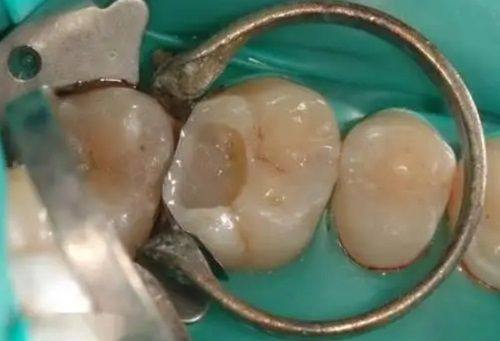

补牙:结合全数字化治疗设备与舒适化诊疗体系,补牙过程轻松,修复成效自然贴合。

微笑青澄口腔门诊部 树脂补牙:280元起